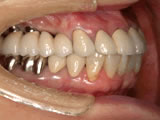

当院では1987年にITIストローマンインプラントによる部分欠損への応用、 また1989年にブローネマルクインプラント用いた無歯顎インプラント治療 (歯がすべてなくなった人へのインプラント治療)を開始しました。

現在までに約2000本のインプラント治療を34年ほど前から行っております。当時はインプラント治療といってもまだ一般的ではなく、「そんな治療聞いたことがない」とおっしゃる患者様が多く、インプラント治療をお受けになる方は少なかったです。最近では「私の場合はどんな治療がいいのですか?入れ歯かインプラントかどっちがいいですか?」と、ご相談にいらっしゃる患者様が増えています。

昨今、人体の再生医療の進歩には目を見張るものがあります。それに伴い骨の再生の研究が進み、インプラント治療も進化しつづけております。1980年代以後、現在に至るまで世界中でいろいろなインプラントが開発されております。その中から当院では現在ブローネマルクインプラント、ライフコアーインプラント、 スプラインインプラント、GCインプラントなどのインプラントを使用しております。